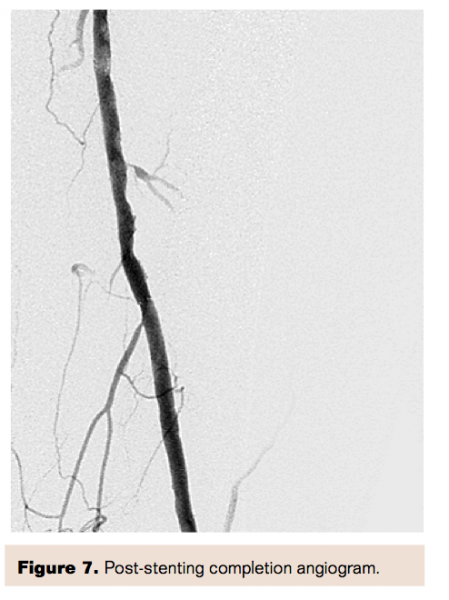

Intravascular ultrasound (IVUS) confirmed the size, extent, and length of the plaque. Stenting of this lesion thus required two Zilver PTX (Cook Medical) stents. A 6 mm x 80 mm stent was placed in the distal SFA, and a 7 mm x 80 mm stent was placed just proximal to the first. The stents were post-dilated with a 6 mm angioplasty balloon with an excellent angiographic and hemodynamic result (Figure 7). Completion hyperemia measurements showed a pressure gradient of 1 mmHg and a ratio of 1.0 (Figure 8, Table 1).